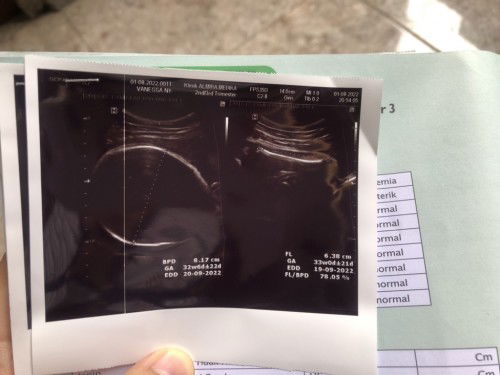

Hamil 33weeks bbj 2,2kg apakah normal?

kata dokternya normal atau engga bu?